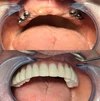

علاج الزرعات السنية